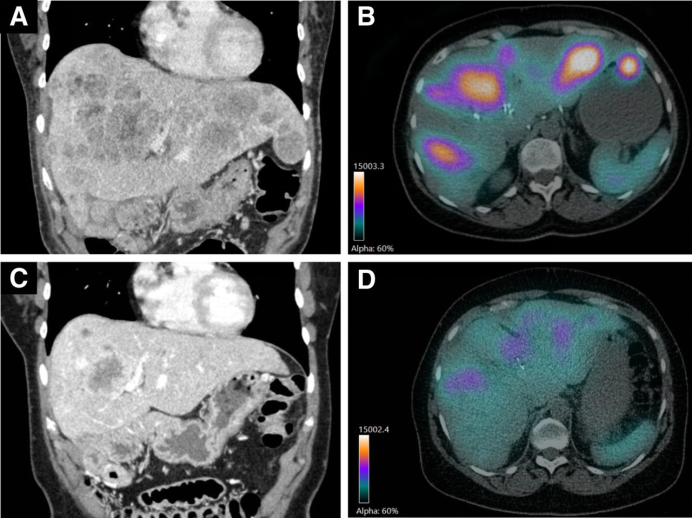

圖示為一名62歲的女性患者,接受了3個【90Y】Y-DOTATOC和1個【177Lu】Lu-DOTATOC治療周期(總活性為26.7 GBq),在18個月的觀察中,有超過15個月受益。基線CT掃描(圖A)和【90Y】Y-DOTATOC二個治療周期的SPECT/CT(圖B)顯示多發性肝轉移。根據RECIST 1.1(圖C),第二個治療周期后的CT掃描顯示部分腫瘤反應,腫瘤負荷顯著降低。與【90Y】Y-DOTATOC 第二個治療周期的SPECT/CT(圖B)相比,【90Y】Y-DOTATOC第四個治療周期SPECT/CT(圖D)顯示肝轉移中的【90Y】Y-DOTATOC攝取減少,這也表明治療反應。